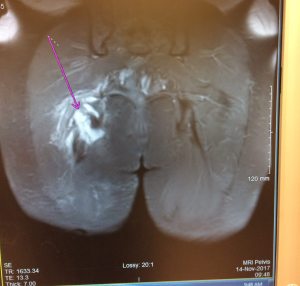

Look, Hamsters. The wound *is* where the light enters you. At least on an MRI… (‘scuze my backside) Happy Thanksgiving from here in the ‘States. I’m so grateful for this community and all the stories you share. Have a happy day.

Yesterday, in preparation for my second opinion with Dr. Price, I picked up a copy of my MRI on CD, and a paper copy of the report.

And this is why I am in so much f-ing pain.

It’s affirming (I am not the biggest cry baby in the land; it’s truly a hot mess in there) if a wee bit horrifying (“stumps”?! Eeek!

). It certainly matches the spectacular bruising I’ve had across my backside.

The bright side… my semimembranosus is intact. Woo-hoo! One monkey still clinging to the branch.

My MRI showed a complete tear of the biceps femoris & semitendinosus tendons, retracted about 2.5-3 cm. My orthopedist has done several proximal hamstring repairs, but she regularly does rotator cuffs & knees. She is supporting my seeking a second opinion with someone who does the procedure more often. So I’m waiting for an appointment on 11/27 with another surgeon, which means no surgery until after Thanksgiving.

I met with Mass. General’s Dr. Price on Tuesday for my second opinion. Looking at my MRI, he thinks I tore all three hamstring tendons, not just the two that the MRI initially reported. I went big after all.